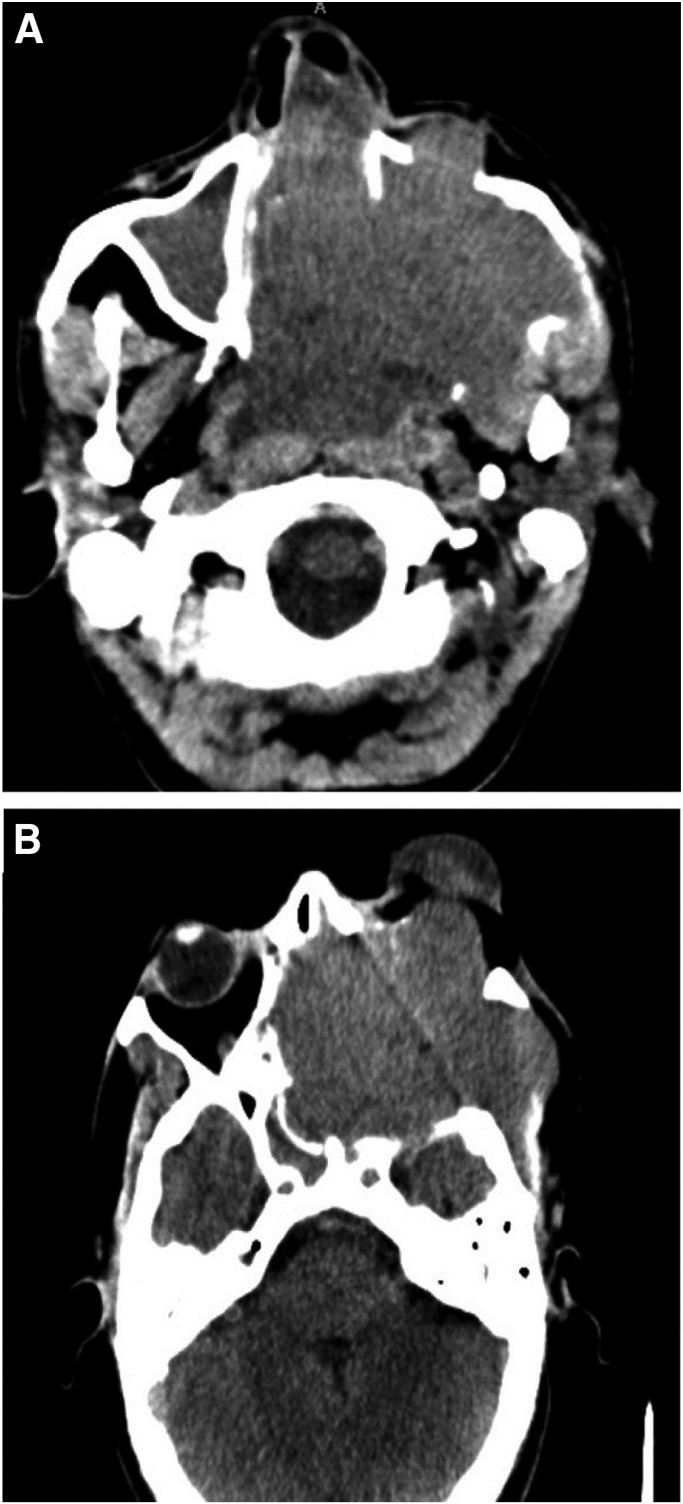

Sinonasal leiomyoma is an exceptionally rare neoplasm arising from smooth muscle cells within the sinonasal tract. This abstract presents a case study of a 43-year-old male patient diagnosed with sinonasal leiomyoma, a distinctive and challenging entity in otolaryngology. The patient presented with a complex clinical history, including a 2-year interval between initial evaluation and definitive diagnosis. Initial histology suggested a smooth muscle tumour of uncertain malignant potential, highlighting the diagnostic intricacies associated with this condition. The radiological assessment revealed an extensive soft tissue mass with the involvement of multiple adjacent structures. The patient subsequently underwent surgical resection, leading to a revised histological diagnosis of leiomyoma. This case underscores the diagnostic challenges associated with sinonasal leiomyoma, emphasising the importance of comprehensive evaluation, including clinical history, radiological imaging, and histopathological examination. Long-term follow-up is essential for monitoring potential recurrences and optimising patient outcomes. By presenting this rare case, we aim to contribute to the limited body of literature on sinonasal leiomyoma and highlight the complexities surrounding its diagnosis and management in clinical practice.